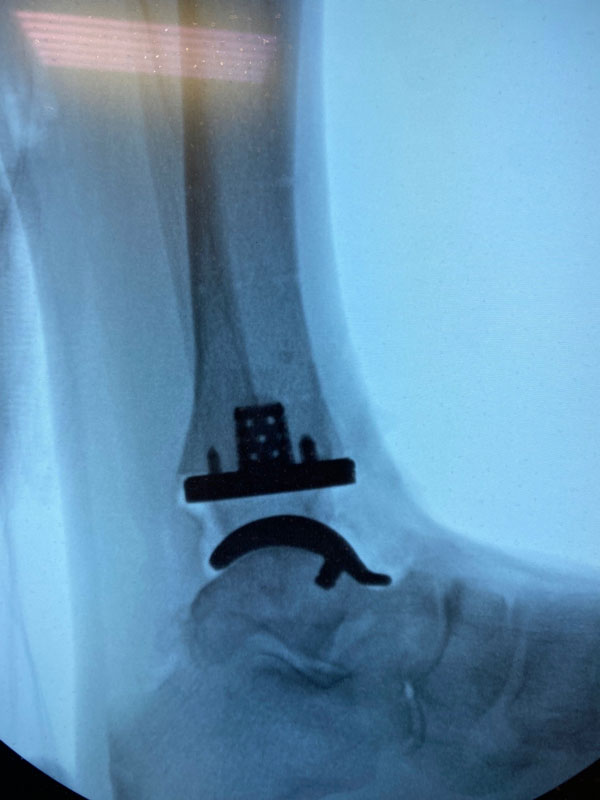

Exactech’s Vantage Ankle 3D and 3D+ tibial implants provide surgeons with tibial stem heights from 10 to 30mm and the added benefits of 3D printing. Additive manufacturing creates a surface that mimics the trabecular nature of cancellous bone. Along with the 3D-printed surface, the implants also feature spiked pegs and a tall sharp central cage, with growing diameters, to aid with initial fixation.

“After several years of developing the 3D+ tibial component with the outstanding Exactech engineers and other design team surgeons, Jim, Jim [Lachman] and I are pleased how the new tibial components and instrumentation seamlessly melded with the existing talar component options. The additive manufacturing, and the press-fit pegs and augmented central cage afford satisfying initial tibial component stability. Particularly exciting is how the intuitive instrumentation allows for reliable and reproducible insertion of a stemmed tibial component through a routine anterior ankle surgical approach.”